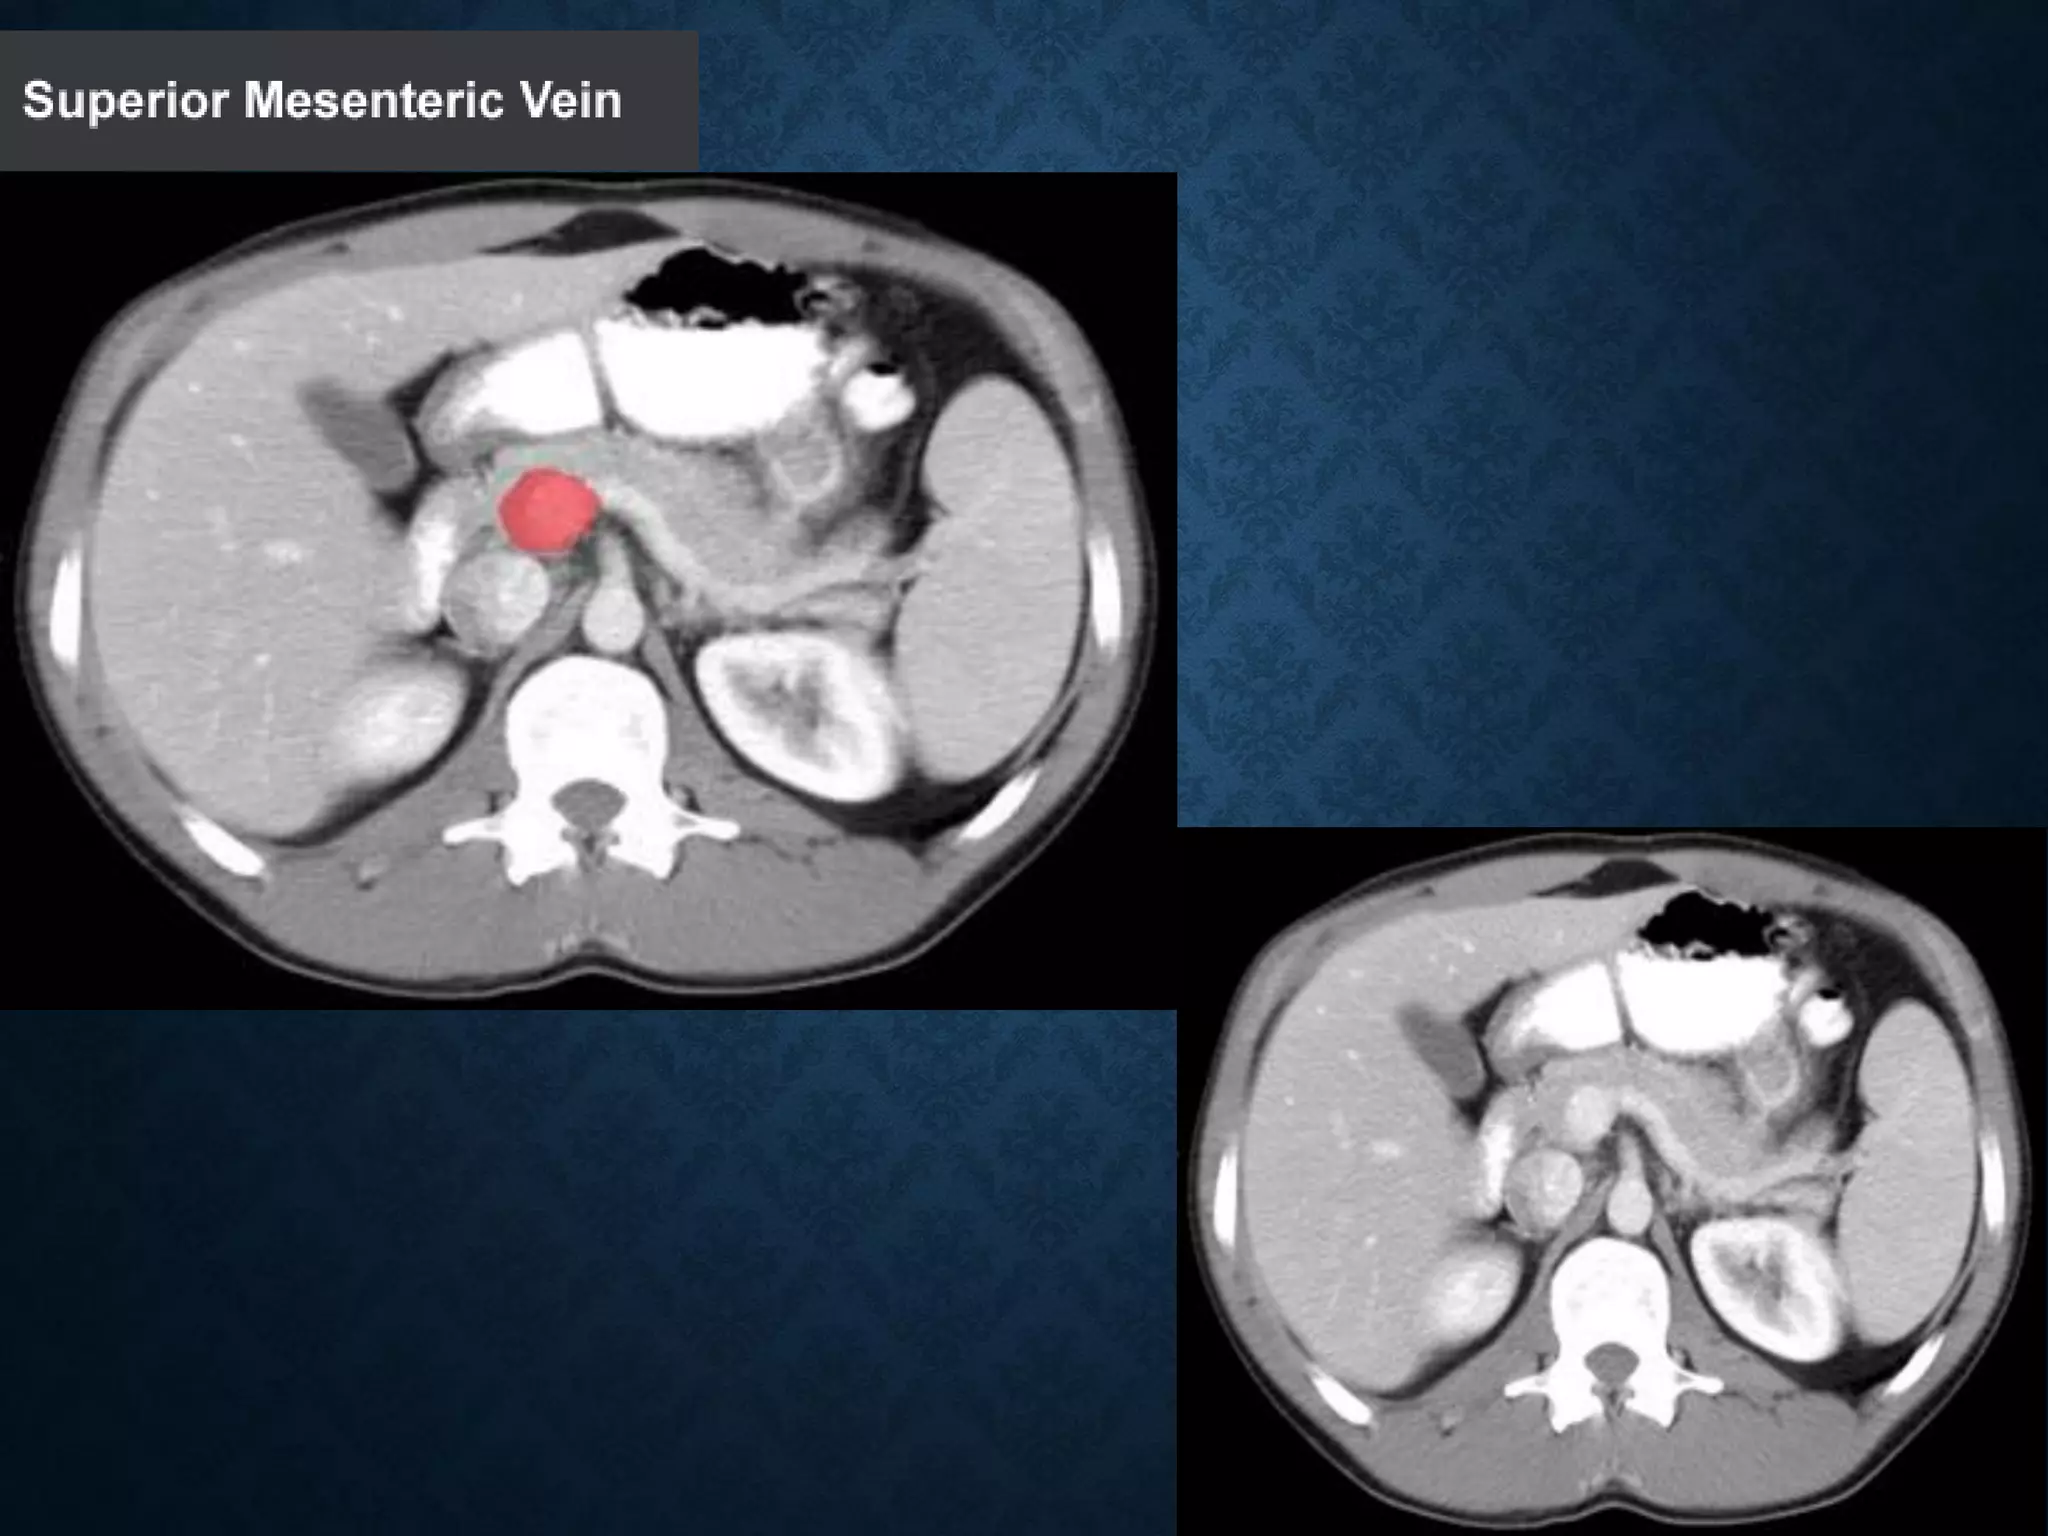

SUPERIOR MESENTERIC VEIN

• In anatomy, the superior mesenteric vein (SMV) is a blood vessel

that drains blood from the small intestine (jejunum and ileum).

• At its termination behind the neck of the pancreas,

• the SMV combines with the splenic vein to form the hepatic portal vein.

• The SMV lies to the right of the similarly named artery, the superior

mesenteric artery, which originates from the abdominal aorta.

SUPERIOR MESENTERIC VEIN •In anatomy, the superior mesenteric vein (SMV) is a blood vessel that drains blood from the small intestine (jejunum and ileum). • At its termination behind the neck of the pancreas, • the SMV combines with the splenic vein to form the hepatic portal vein. • The SMV lies to the right of the similarly named artery, the superior mesenteric artery, which originates from the abdominal aorta.